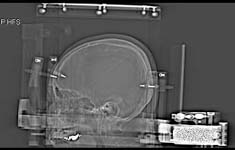

³úÁ¤À§

¼ö¼ú¿ë Ʋ(Leksell frame)

³úÁ¤À§¼ö¼úÀÇ

±âº»¿ø¸®: »ïÂ÷¿øÀûÀÎ °ø°£°³³äÀ» ÀÌ¿ëÇÏ¿©

º´º¯ÀÇ Á¦°Å ¹× Ä¡·á·Ê

³ú³»Ç÷Á¾È¯ÀÚ¿¡¼ÀÇ

½Ã¼ú·Ê

½Ã¼úÀ»

À§ÇÑ ³ú CTÃÔ¿µ ¼Ò°ß ¹× ¼ö¼ú ÈÄ Á¾¾ç³»

Žħ(probe)ÀÌ »ðÀÔµÈ ¸ð½À